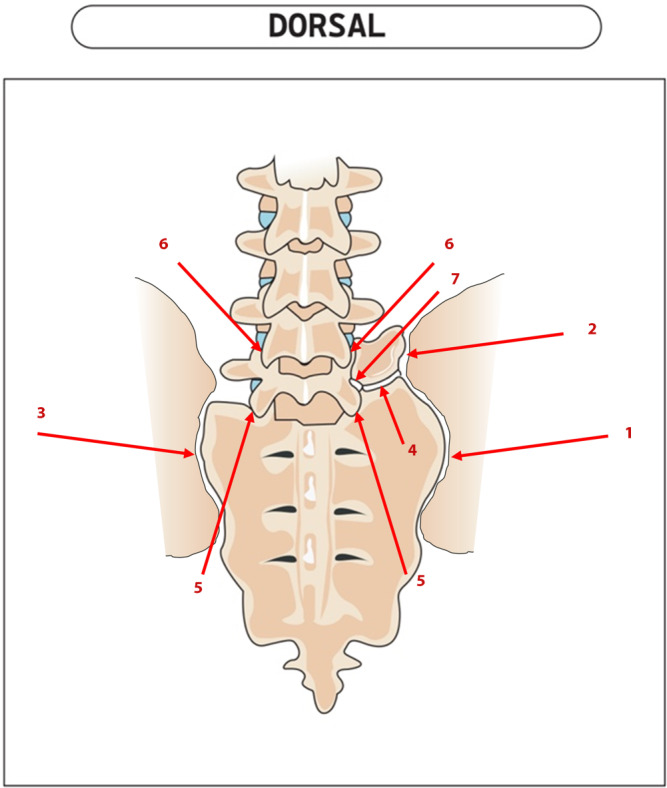

Background: Lumbosacral transitional vertebrae (LSTV) are common, with a prevalence of 15-35%, and can be a cause of specific low back pain. The insufficient awareness of this anomaly often leads to delayed diagnosis and treatment.

Results: Patients with symptomatic Bertolotti syndrome often suffer from chronic low back pain and radiculopathies. Imaging techniques, particularly X‑rays and MRI, play a key role in diagnosis. Conservative treatments show limited success. Surgical resection of the transverse process (processectomy), especially after positive test infiltrations, leads to significant pain relief, particularly in younger patients without degenerative changes.